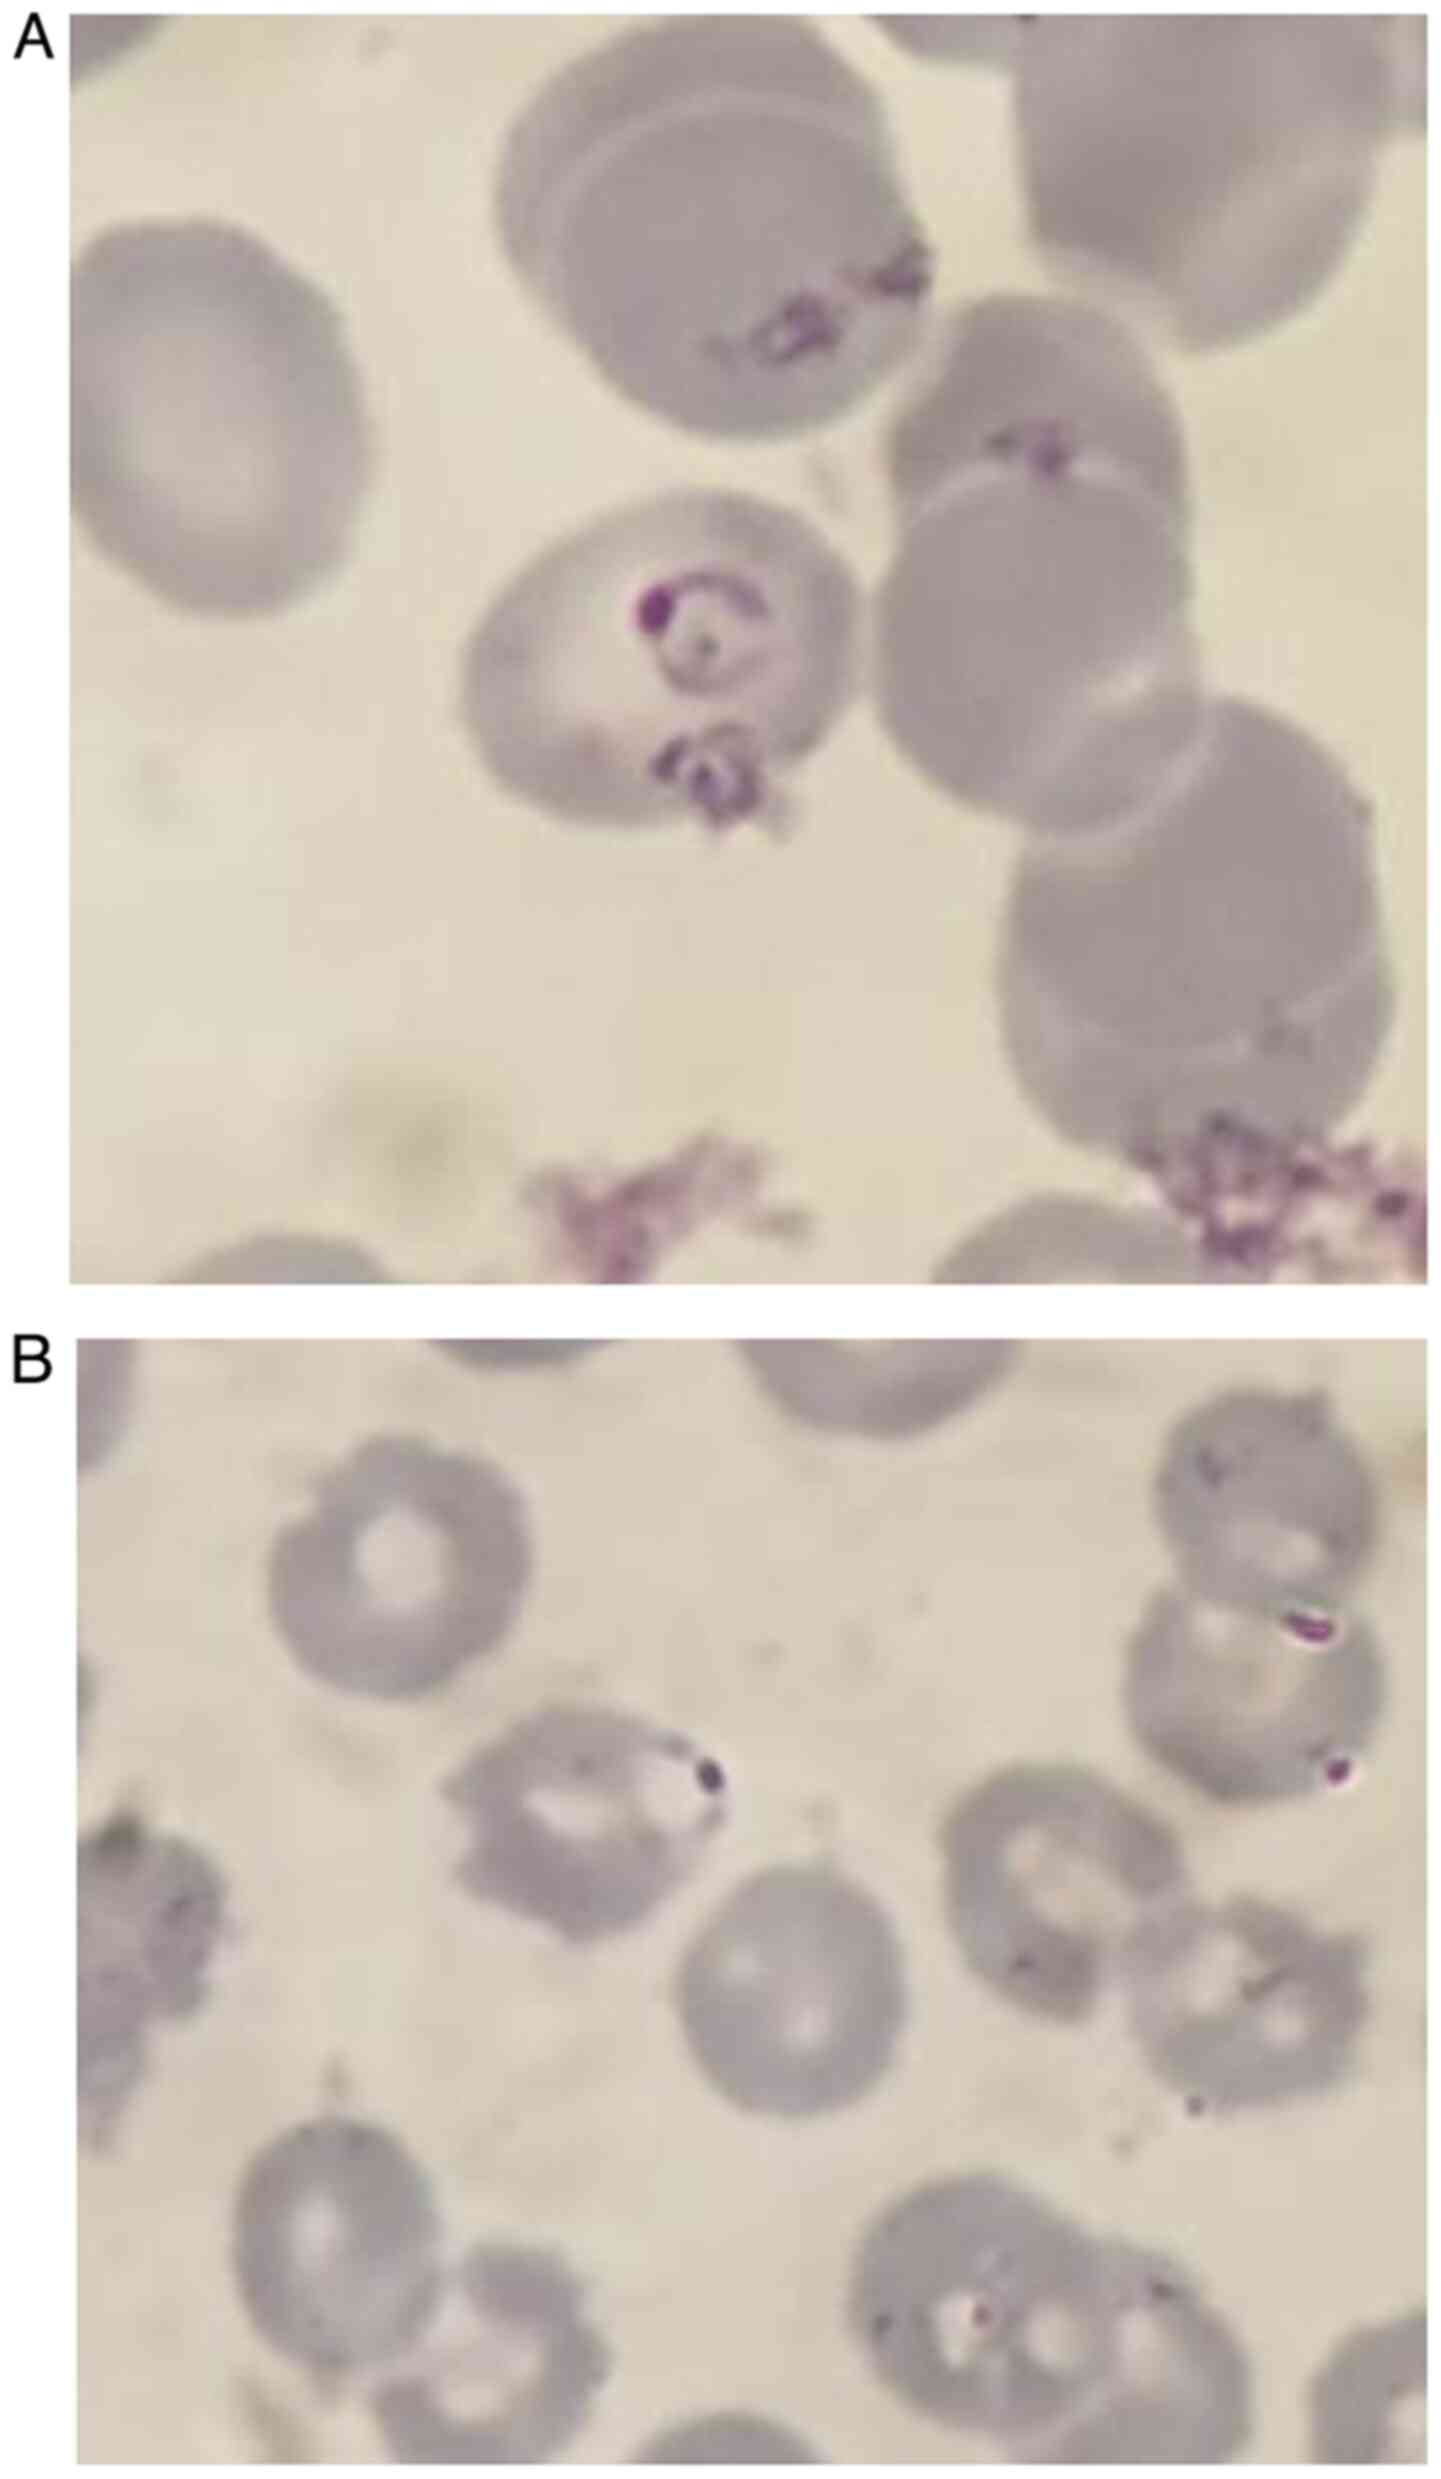

The thin smear (Fig.

2) revealed ring-shaped trophozoites, normal-sized erythrocytes

and rare banana-shaped gametocytes. P. falciparum malaria

was diagnosed. This result was confirmed by two further tests,

performed at 8 and 12 h following the first test and the beginning